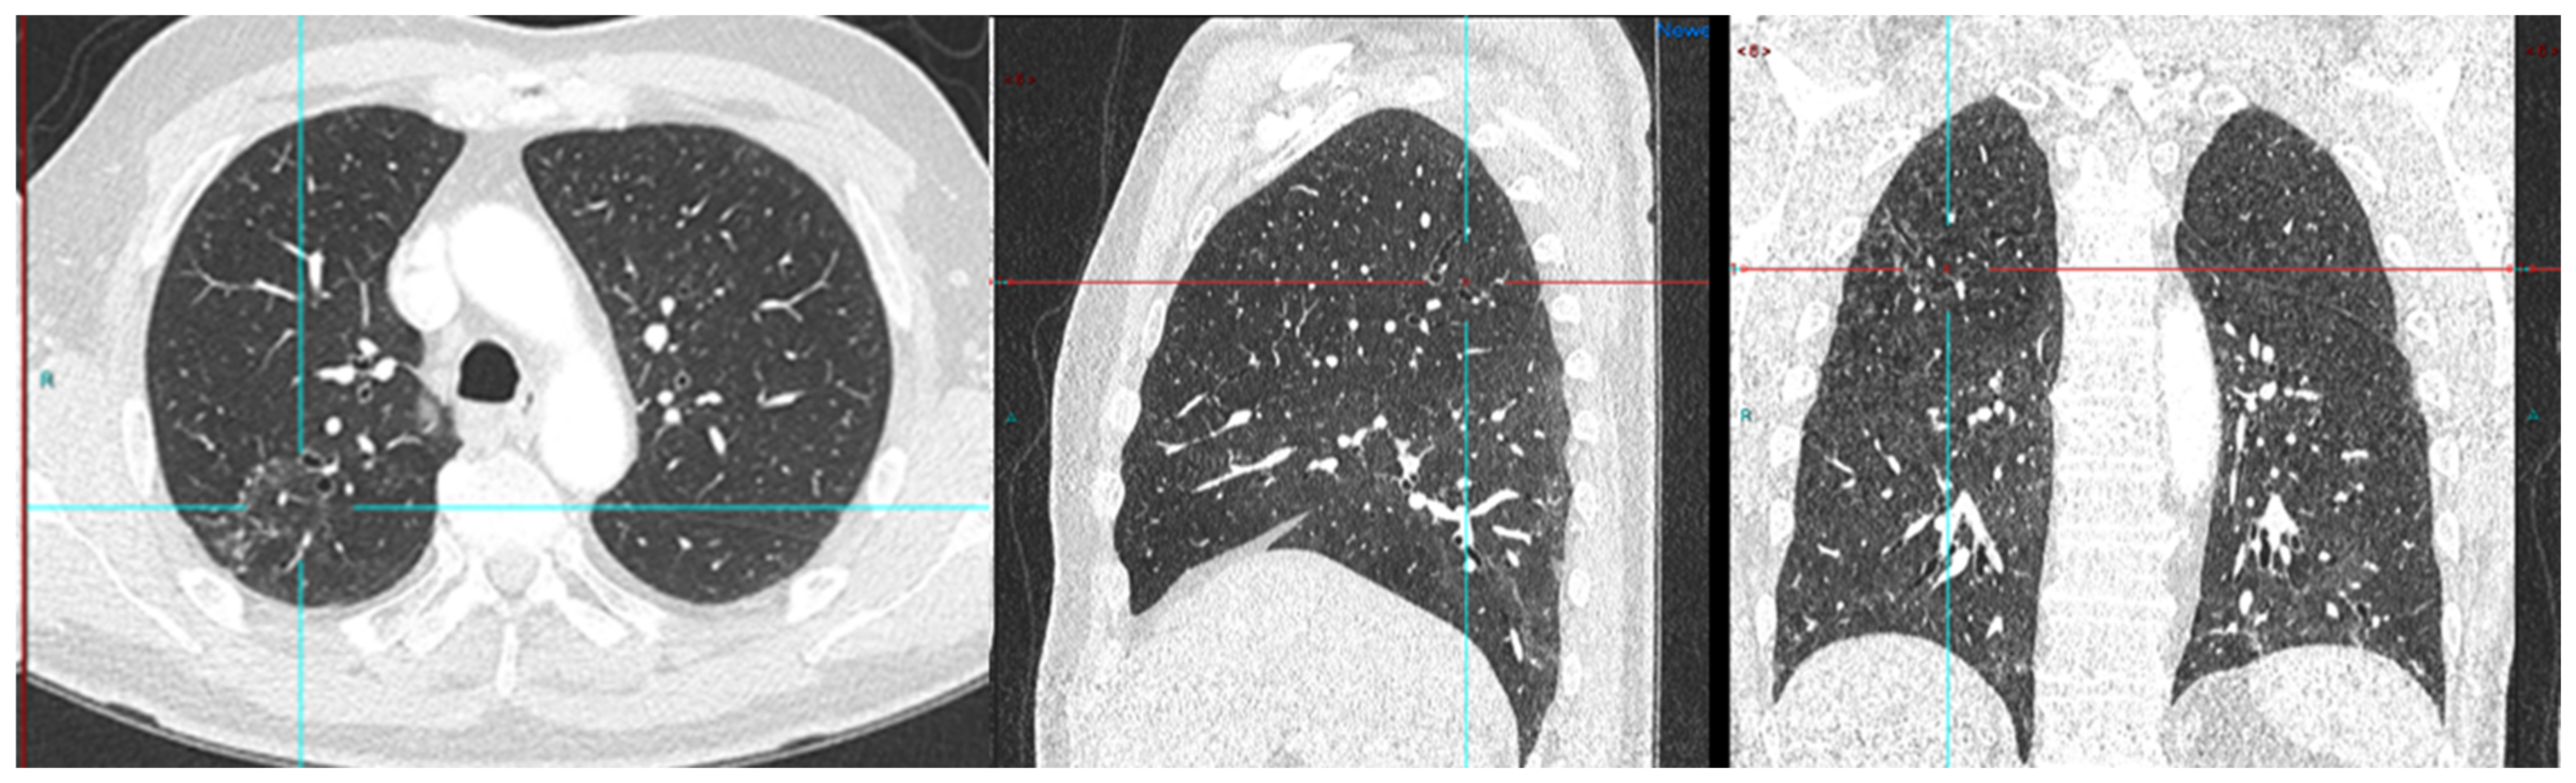

We conducted a separate subgroup analysis of 61 patients (Table 4) who had repeat imaging. Thirty had indeterminate findings on initial PSMA PET CT and the findings changed to a positive lesion in 14 (10 with known small indeterminate pelvic lymph node and four with known indeterminate prostate focus, PSA increase of 0.7 to 3.0 in 6 months), negative in eight (four with pelvic lymph node, four with uptake in bones on prior PET CT, PSA increase of 0.13–2). Six patient had the same indeterminate small pelvic lymph node, two had the same indeterminate retroperitoneal lymph node (PSA increase of 0.4 to 2.5). Overall, the follow-up PSMA PET CT was able to conclude in 24/30 patients on follow-up. Of the 31 patients who had repeat PSMA PET CT scans done for a further rise in PSA levels (PSA rise range 0.3–10), 24 had new lesions (prostate lesion in four, prostate and seminal vesicle involvement in four, pelvic/retroperitoneal lymph nodes in 12, new bone lesion in four) and eight had negative scans even on repeat imaging (PSA rise 0.3–2.3). For example, patient in Figure 2 had negative scan at PSA of 3.4 ng/mL, PSA velocity of 1.3 ng/mL in six months. The uptake in right humerus is at the site of known prior humerus fracture and therefore it was categorized as PSMA RADS 1 B (7). Another patient in Figure 3 had and indeterminate lymph node at PSA 6.5 ng/mL, after rise of 3 ng/mL in 2 years, it was categorized as RADS 3A(7). An interesting finding in this case was the consolidation changes in the right upper lobe, which resolved in a follow-up CT performed after 2 months (Figure 4).

Figure 3.

Radical prostatectomy negative scan at PSA 3.5 ng/mL, indeterminate lymph node at PSA 6.5, rise of 3 ng/mL in 2 years RADS 3A—RP status. Consolidation in right upper lobe. Resolved on follow up CT after 2 months.